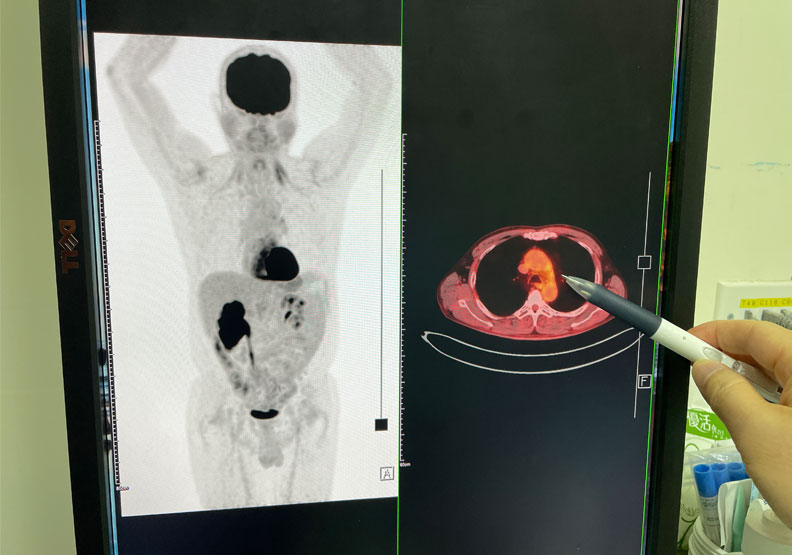

除此之外,也趁勝追擊一步一步地把癌細胞縮小,安排正子電腦斷層掃描,竟然發現先前在左上肺和轉移到縱膈腔、頸部淋巴腺一大片的癌細胞,都已經完全消失不見了,僅需1年半治療小細胞肺癌,成功把癌細胞全部殺死。